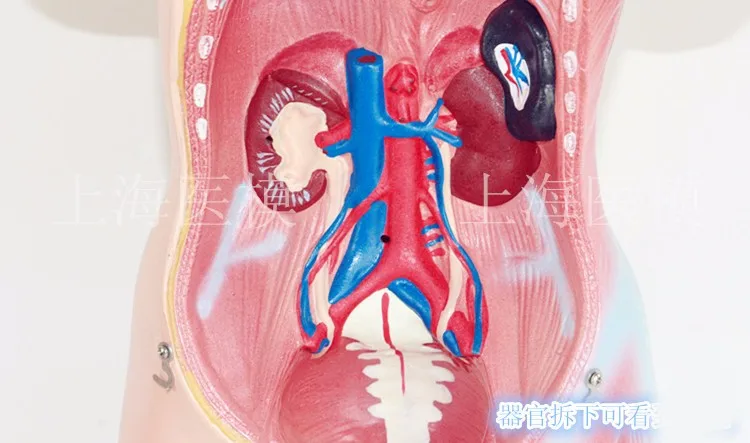

45CM uniex human Torso human anatomical structure model internal organ model 23 parts